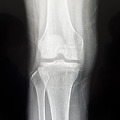

• 무릎연골손상줄기세포치료 카티스템 30일차

연골은 엑스레이로는 보이지 않지만 무릎뼈 사이 빈공간에 있으며 약1년 정도의 시간이 지나야 온전이 자기의 연골이 된다고한다. 이제부터는 한걸음 한걸음 걸으며 다리 근육을 키우고 목발 없이 혼자 걷는 날만 기다리면 된다.